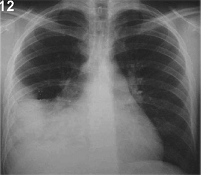

DERRAME PLEURAL Radiopacidad que se distribuye hacia abajo si el paciente está de pie, con curva de Damoisseau. |